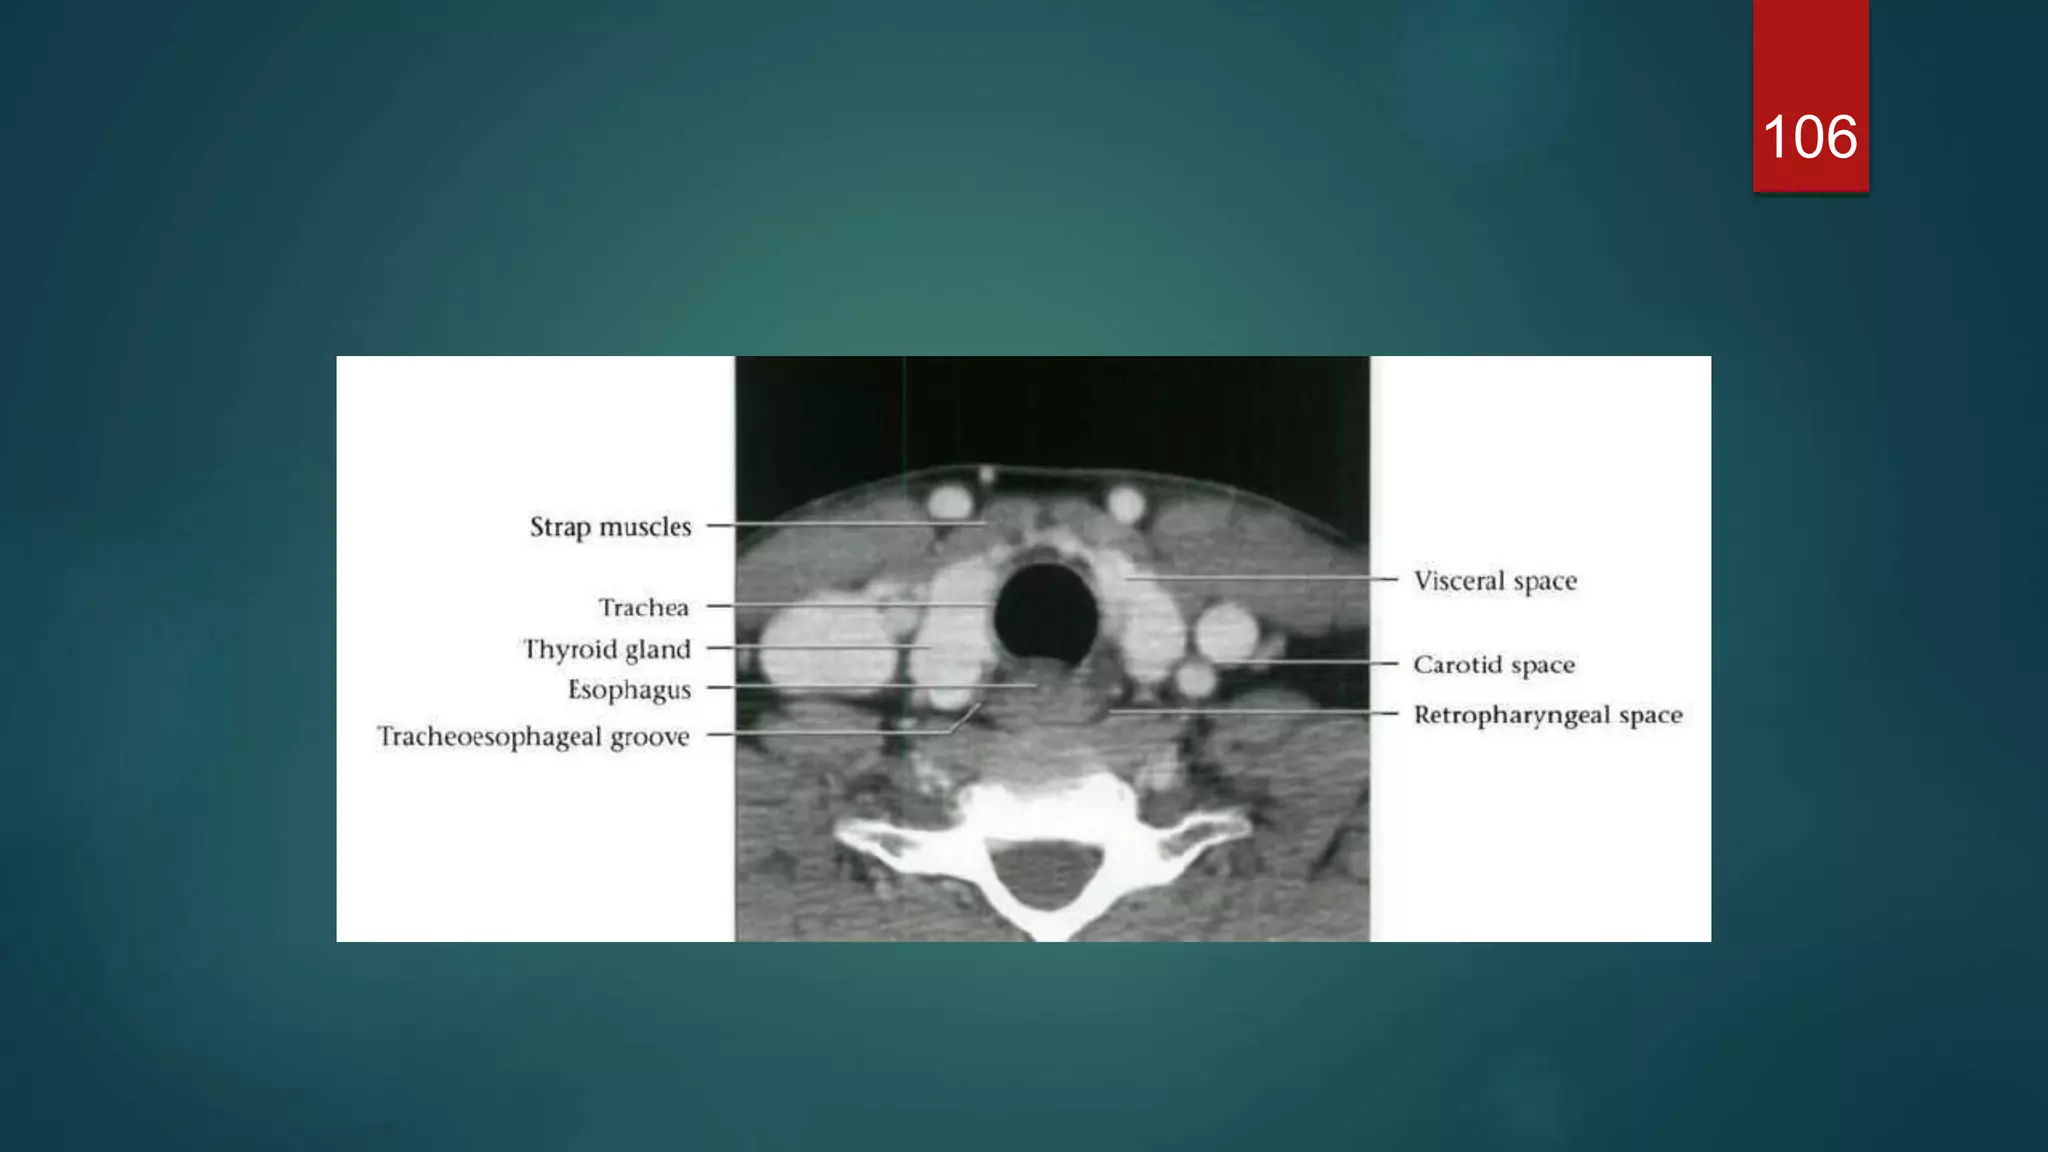

Visceral space

 The visceral space extends from the hyoid bone to the superior

mediastinum (level of aortic arch / T4), and is surrounded by the middle layers

of the deep cervical fascia.

 Extend from hyoid bone to superior mediastinum

 Contents

• thyroid gland

• parathyroid gland

• oesophagus

• larynx

• hypopharynx

• trachea

• recurrent laryngeal nerve

• lymph nodes (level VI)

106